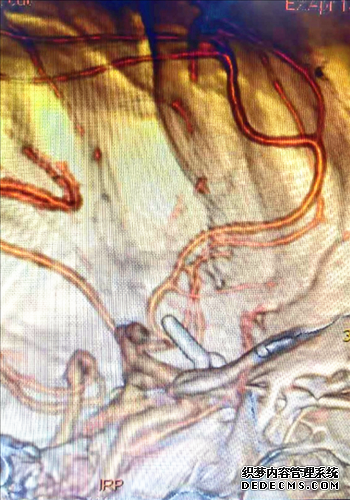

此次手术获益的患者为51岁的梁先生,因高血压脑出血入院,进行脑血管疾病筛查时,头颈部CTA及DSA脑血管造影检查提示前交通动脉瘤。该动脉瘤系未破裂动脉瘤,但形态不规则,随时有动脉瘤破裂出血风险。文献报告其一旦破裂有1/3的人连就医的机会都没有会立即死亡,故神经外科医师将这种动脉瘤将之比作脑袋里的“不定时炸弹”。

对这种“不定时炸弹”目前綦江区人民医院神经外科既能开颅夹闭也能介入栓塞。由于梁先生家庭经济不宽裕,没法接受介入治疗,只能选择开颅夹闭。鉴于梁先生对常规骨瓣开颅的恐惧,綦江区人民医院神经外科团队为其量身设计了一种无需剃发、切口(4cm)在眉毛上的微创开颅,即锁孔微创开颅。

术前由医务部牵头组织MDT团队充分讨论及与家属充分沟通情况下,于4月8日由神经外科李栋良主任医师、张宇副主任医师在麻醉科团队紧密配合下,行“左侧眉弓开颅锁孔入路前交通动脉瘤开颅夹闭术”,手术顺利,成功为梁先生拆除了脑袋里的“炸弹”。